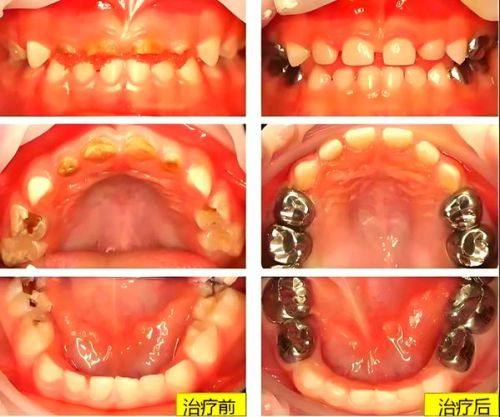

儿童牙齿美学修复:针对儿童口腔特点,兼顾美观与健康,采用温和的诊疗方式,在改善牙齿美观的同时保护儿童口腔健康,让孩子更易接受诊疗过程,避免孩子对看牙产生恐惧。

乳牙、年轻恒牙诊疗:擅长儿童乳牙龋病、年轻恒牙牙髓病等常见儿童口腔问题,操作轻柔细致,及时干预口腔问题,保护儿童牙齿健康。